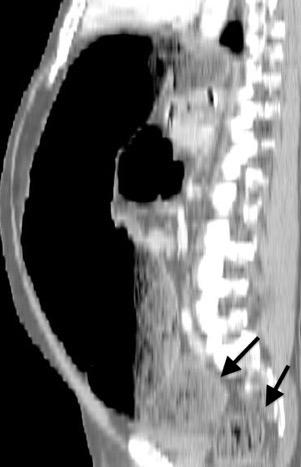

Hallazgos en RM .

Buena en casos dudosos

Cortes sagitales y coronales: Interrupción de la línea diafragmática

Paciente que ingresa con síntomas de colecistitis aguda. Antecedentes de trauma importante muchos años antes

Zhao L et al. Delayed traumatic diaphragmatic rupture: diagnosis and surgical treatment. © Journal of Thoracic Disease.

J Thorac Dis 2021

Asas

Líquido pericolecistítico

V. biliar con cálculos

Diafragma